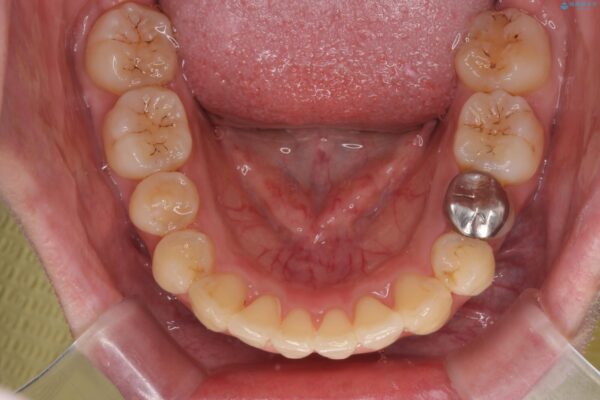

治療を終えて

患者様の協力度も高く、リファインメントなしで治療を終えることができました。

抜歯をしない場合、多くは歯と歯の間を少し削ることでスペースを作ります。

動的治療期間は約4か月となり、短い治療期間で前歯のガタつきが改善され大変喜んでいただけました。

治療後

気になる犬歯のガタつきをマウスピース矯正で改善 治療後画像 気になる犬歯のガタつきをマウスピース矯正で改善 治療後画像 気になる犬歯のガタつきをマウスピース矯正で改善 治療後画像 気になる犬歯のガタつきをマウスピース矯正で改善 治療後画像